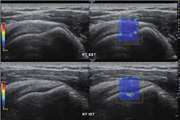

بررسی یافتههای سونوگرافی و سونوالاستوگرافی shear wave تاندون اشیل در بیماران مبتلا به اسپندیلوآرتروپاتی سرونگاتیو و تعیین ارتباط یافتهها با فعالیت بیماری در بیماران مراجعه کننده به درمانگاه روماتولوژی بیمارستان شریعتی 1404/01/17 - 11:07